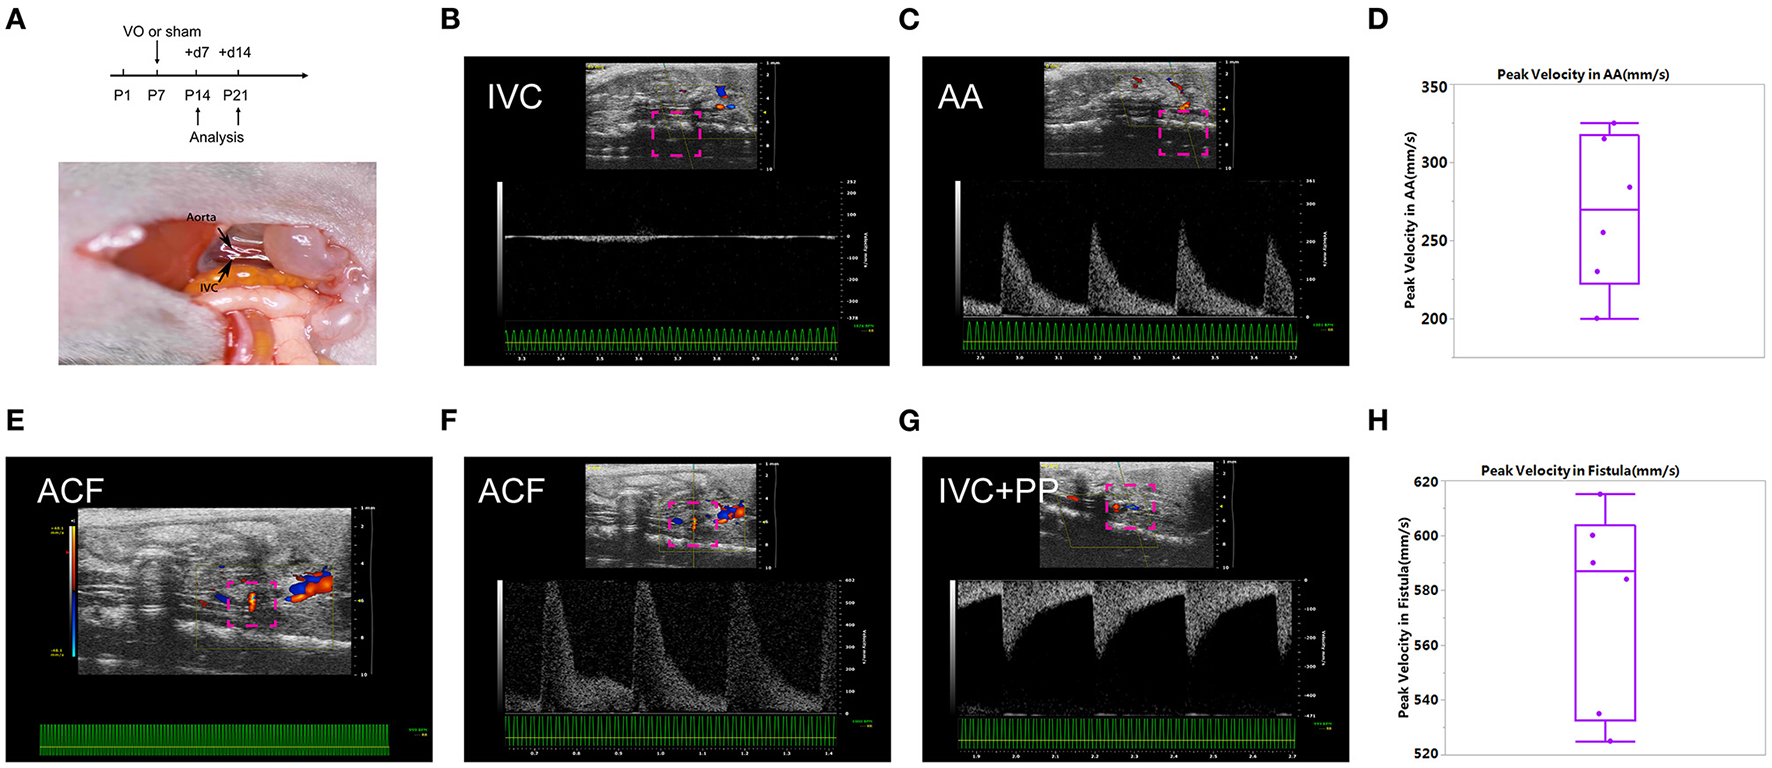

As shown in Figure 1A, we conducted ACF and sham procedures on P7, and performed analyses at P14 and P21. Under normal conditions, at P14, there was no pulsatile blood flow at IVC, while with a pulsatile blood flow at the AA, the peak flow velocity up to 300 mm/s (Figures 1B,C). The average of peak velocity in the AA was 268.2 ± 48.9 mm/s (Figure 1D). At the puncture point, there was a pulsatile blood flow (Figure 1E), with a peak flow velocity up to 602 mm/s (Figure 1F). After punctuation, a pulsatile blood flow appeared in IVC, and the peak flow velocity reached up to 280 mm/s (Figure 1G). The average of peak velocity in the fistula was 574.8 ± 36.4 mm/s (Figure 1H). These results suggested that ACF mice were successfully created, consistent with our previous publications (13, 18, 20).

Figure 1

Establishment of the aortocaval fistula (ACF). (A) Top panel: experiment protocol; bottom penal: schematic diagram of the ACF model. (B) No pulsatile blood flow appears in the inferior vena cava (IVC). (C) Pulsatile blood flow is shown in the abdominal aorta (AA), with a peak blood flow velocity of 250 mm/s. (D) Quantification of peak velocity in the AA. (E) A representative image of blood flow through the fistula. (F) The representative image of pulsating blood flow at the fistula, with a peak blood flow velocity of 602 mm/s, which is higher than that of the AA. (G) Pulsatile blood flow appeared in the IVC after fistula establishment, with a peak blood flow velocity of 280 mm/s. (H) Quantification of peak velocity in the fistula. n = 6 mice.